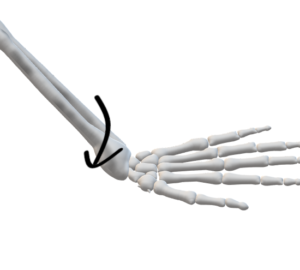

2.スミス骨折(逆コーレス骨折)

(発生)

手背をつき転倒

橈骨遠位端部に強い背側凸の屈曲力

(症状)

➀骨折線の走行

手関節の1~3cm近位の背側かから、やや斜めに掌側近位へ走る

➁遠位骨片の転位

・掌側転位

・橈側転位

・短縮転位

・捻転転位

➂変形

・骨遠位端が背側凸

・掌側転位高度になり、近位骨片に騎乗っかつ短縮転位⇒鋤状変形